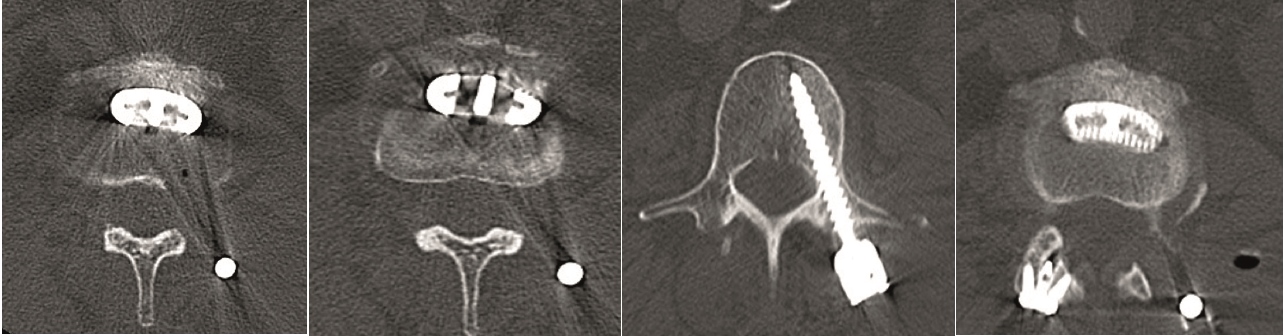

Multilevel facet pathology is shown in Fig 6. Intraoperative and postoperative images are shown (Fig 7-9).

A healthy 66-year-old female patient had been experiencing LBP for 5 years.